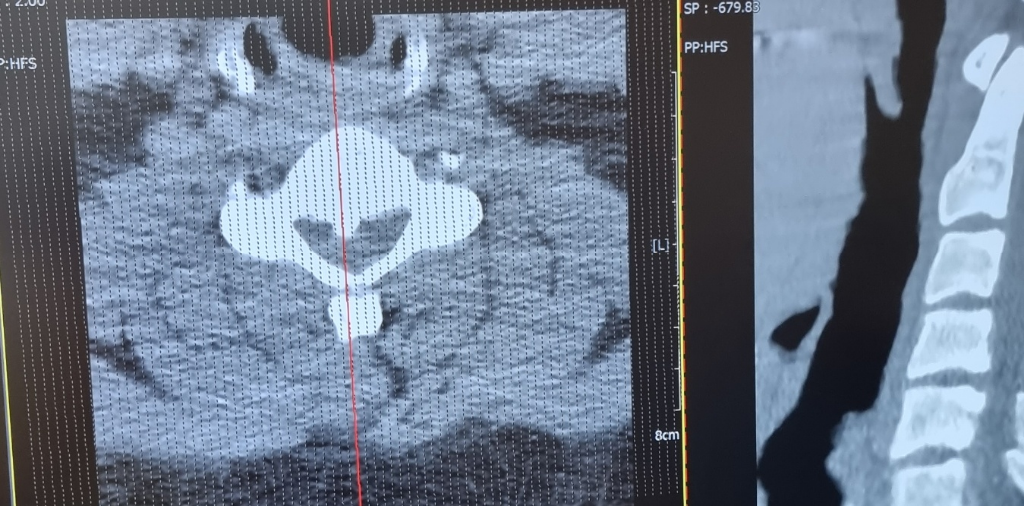

경외과 가서 엑스레이 3 4번 찍고 mri찍어보라해서 찍어보기전에 조금 큰 병원에서 ct를 찍고 사진을 보며 얘기를 나눴는데 팔이왜따가운지 설명도 잘 못해주고 물리치료받아라 뭐 나중에 100프로 마비온다 시간의문제다 하더니 또 마비안올지 올지 자기도모른다 여튼 애매한 답만을 듣고 인터넷에 글을올리니 후종인대 골화증같다하고 증상도 보니 맞아떨어집니다 다행히 심각한 단계는 아닌거같고 팔 다리 힘떨어짐이나 배변문제 그런것들은 없는데 이제 도수치료도 열심히받고 살도빼고 담배도 끊으려 합니다 자세도 신경쓰고요 요 2달 우울했는데 이렇게만 지내서는 안될거같아서 힘을내려합니다.. 일단 저 인대?가 더 자랄수도 있나요? 어떻게 치료해야지 최악의 경우인 수술까지 가지않을수 잇을까요?